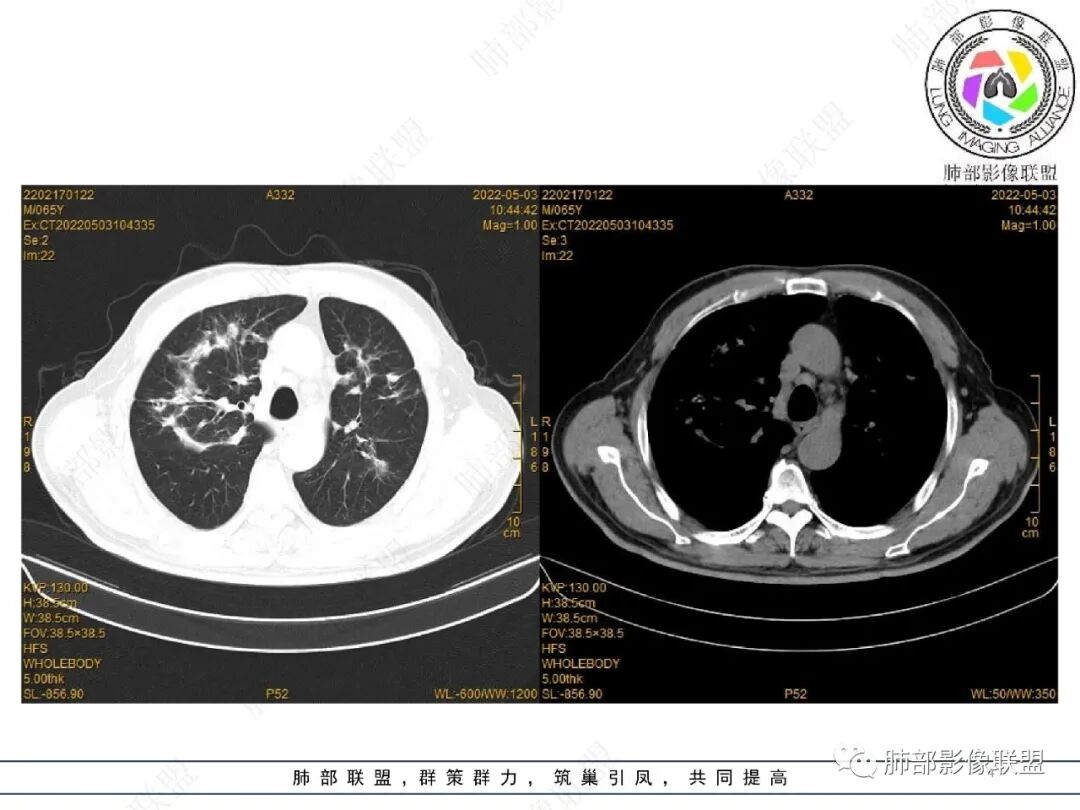

2022.2.17CT显示两肺中内带多发结节影、斑片影、条索影,部分病灶侧向融合与胸膜平行。部分病灶沿着支气管血管束分布、其内支气管稍扩张。部分病灶呈反晕征。大部分病灶边界显示清晰,部分病灶周围可见边界不清的GGO。2022.4.12CT显示两肺中内带多发结节影、条索状、条带状高密度影,边界收缩平直凹陷,大部分病灶沿着支气管血管束分布,亦有位于胸膜下侧向融合与胸膜平行的病灶。总体与第一次CT对比两肺病灶明显吸收。

老年男性,两肺多发病灶,整体呈OP样改变,至于是原发性还是继发性的OP,需要临床鉴别。此病例穿刺结果是隐球菌。该病例CT上缺乏隐球菌典型的“在那遥远的胸膜下,多个蘑菇兄弟,可以侧向融合呈长串状与胸膜平行”影像表现,更多是OP样改变,仅凭临床表现或影像资料诊断隐球菌难度比较大。当然也不除外二元论,导致隐球菌的影像表现被掩盖。